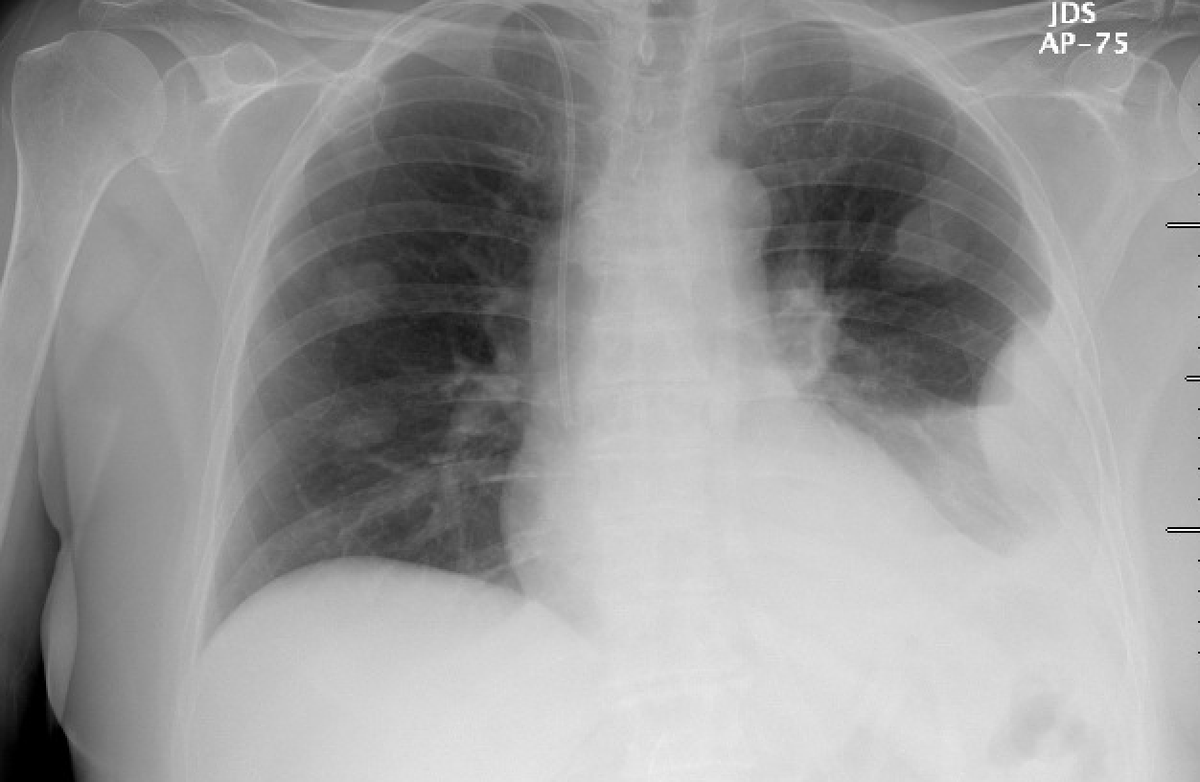

Post thoracentesis effusion (apologies for flipped image). Given uncomplicated procedure, routine CXR not performed based off the following guidlines: https://www.journalofhospitalmedicine.com/jhospmed/article/157109/hospital-medicine/recommendations-use-ultrasound-guidance-adult,

4/

Called approximately 3 hours later to re-evaluate patient who was experiencing some left sided pleuritic CP. Vital signs stable, no new O2 requirement, breathing comfortably on RA. Physical exam unchanged.